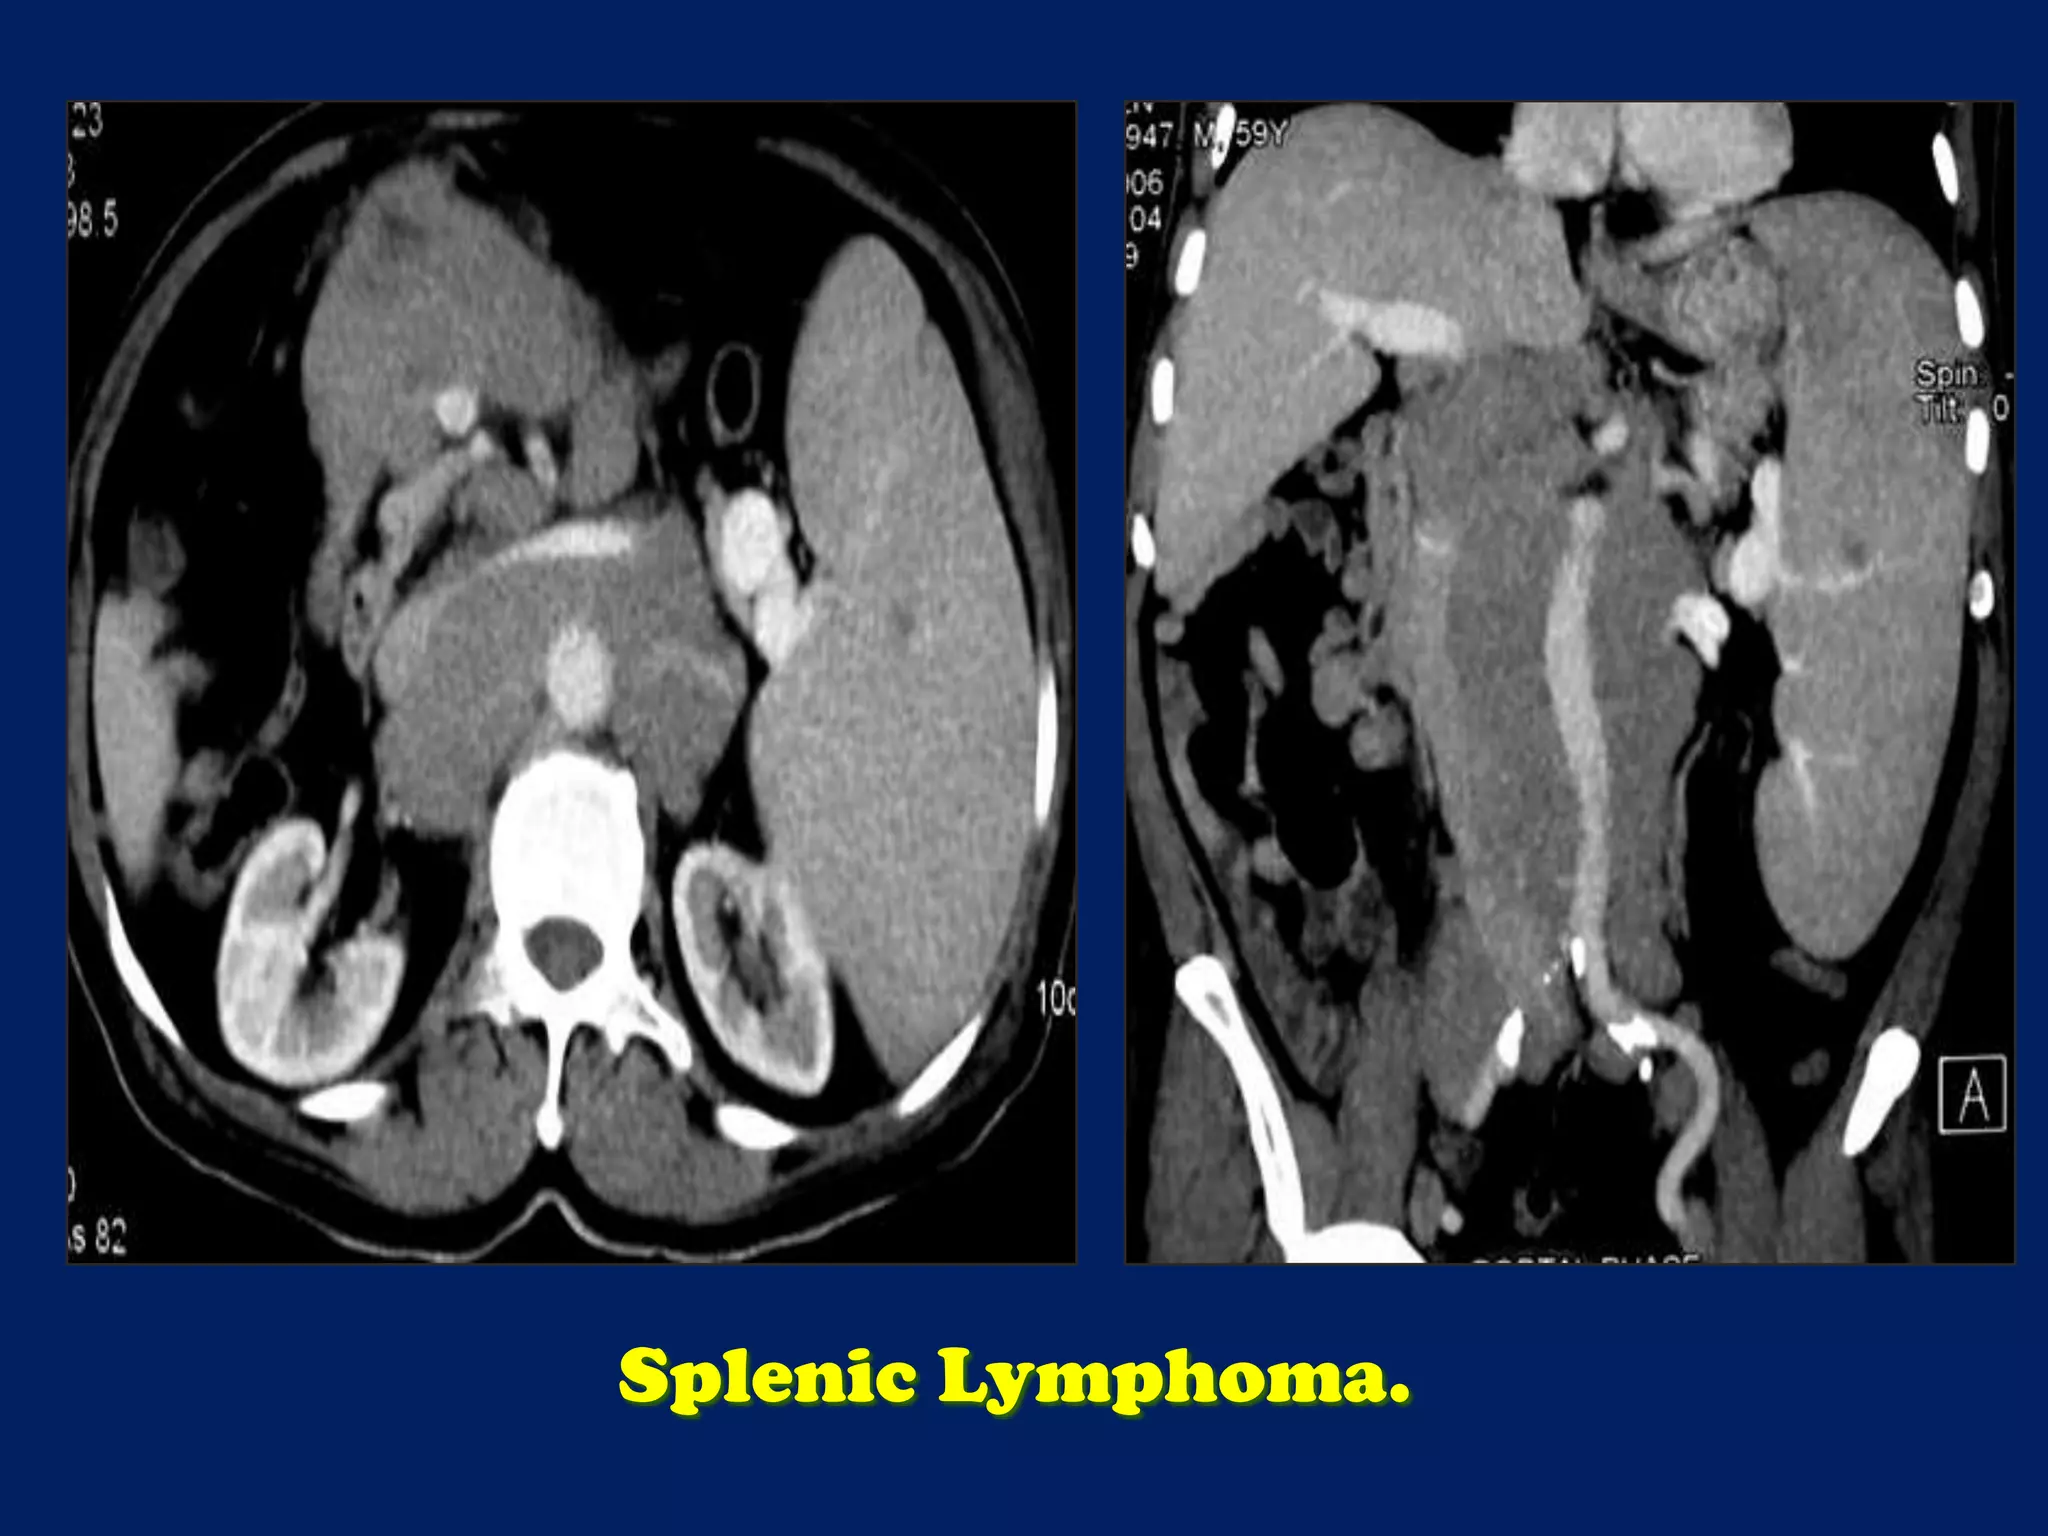

This document discusses imaging of the spleen and summarizes various congenital anomalies and pathologies that can affect the spleen. Some common congenital anomalies mentioned include accessory spleens, asplenia, polysplenia, and splenic fusions. Acquired conditions like repeated infarctions, infiltration, tumors, and cysts can also cause splenomegaly or functional asplenia. Wandering spleen is discussed as a rare congenital anomaly where the spleen lacks attachments and is mobile within the abdomen. Various grades of splenic lacerations and examples of splenic imaging findings are also briefly summarized.